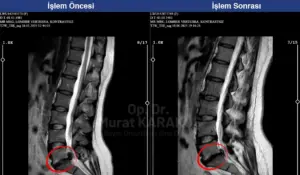

Bel fıtığı nedeniyle bacağa vuran ağrı, uyuşma ve yanma şikâyeti yaşayan birçok kişi çözüm ararken nükleoplasti kelimesiyle karşılaşıyor. Peki nükleoplasti nedir, gerçekten ameliyat mıdır, kimlere uygundur?; fıtıklaşmış disk dokusunun iç basıncını düşürerek sinir üzerindeki baskıyı azaltmayı amaçlayan, ameliyatsız kabul edilen minimal invaziv bir girişimdir. Açık cerrahiye göre daha küçük kesiyle uygulanır ve genellikle aynı gün taburculuk mümkündür.

Burada temel amaç, diskin içindeki fazla basıncı kontrollü şekilde azaltarak sinir köküne olan baskıyı hafifletmektir. Bu nedenle özellikle başlangıç ve orta düzey bel fıtıklarında değerlendirilen bir yöntemdir. Ancak her bel ağrısı olan kişi için uygun değildir. Doğru hasta seçimi, başarı açısından kritik rol oynar.